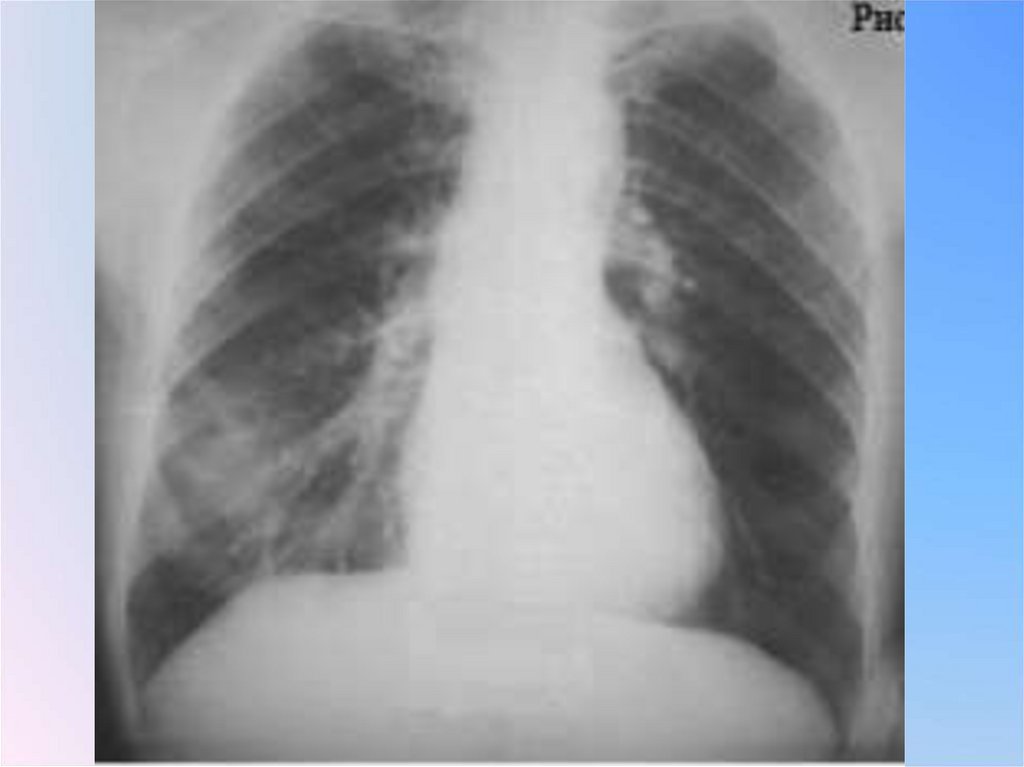

Патоморфологический субстрат шаровидного

образования: 1) туберкулезный инфильтрат;

2) туберкулома (инкапсулированный казеоз);

3) заполненная блокированная туберкулезная

каверна; 4) силикотические узлы; 5) «круглая»

неспецифическая пневмония; 6) недренированный абсцесс; 7) злокачественные опухоли;

лимфомы; 9) доброкачественные опухоли

(наиболее часто гамартомы, содержащие

хрящевую ткань); 10) сосудистые

образования; 11) кисты, заполненные

жидкостью; 12) инфаркт; 13) гематома; 14)

осумкованный экссудат в междолевой плевре

(последний не является истинно легочным, внутрипаренхиматозным образованием, однако, замкнутый листками плевры,

оказывается расположенным внутри легкого)